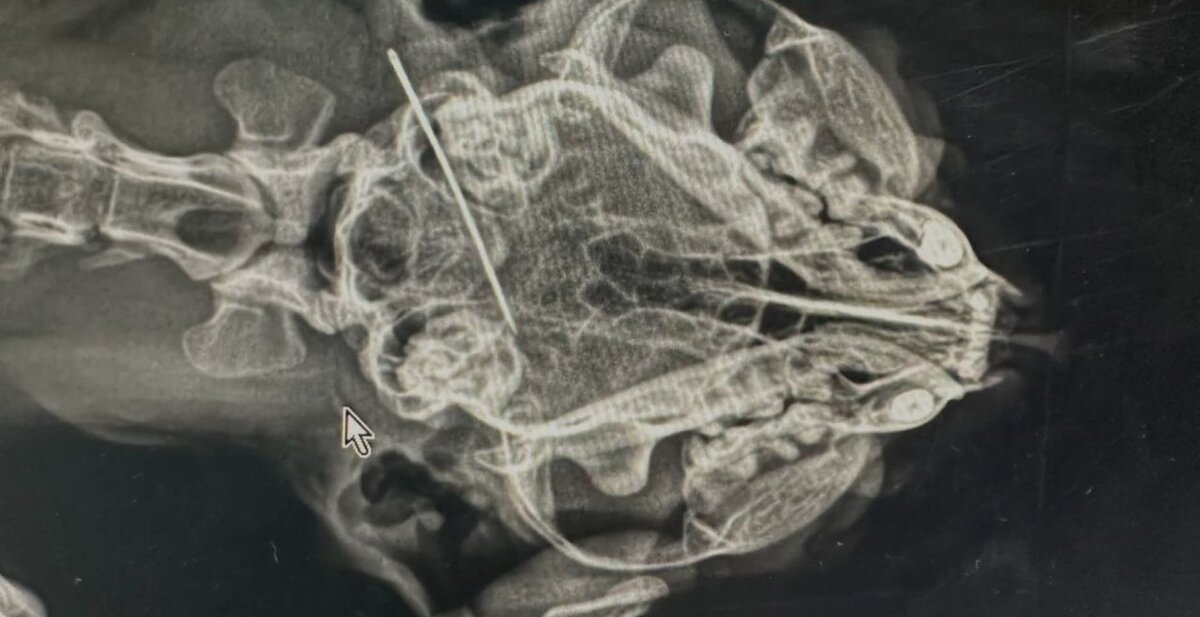

• Нитки и иголки, вся швейная история. Это очень опасно: нити могут порезать кишечник, а иголки — проткнуть стенки органов.

ЧТО ВКЛЮЧАЕТ ДИАГНОСТИКА

• Рентген-исследование.

• УЗИ брюшной полости.

• Эндоскопия (если предмет в желудке).

Если инородное тело (например, сережка или невидимка) находится в кишечнике, может потребоваться полостная операция (лапаротомия). Чтобы избежать подобных случаев, пересмотрите игрушки вашего питомца и уберите опасные предметы из зоны доступа.